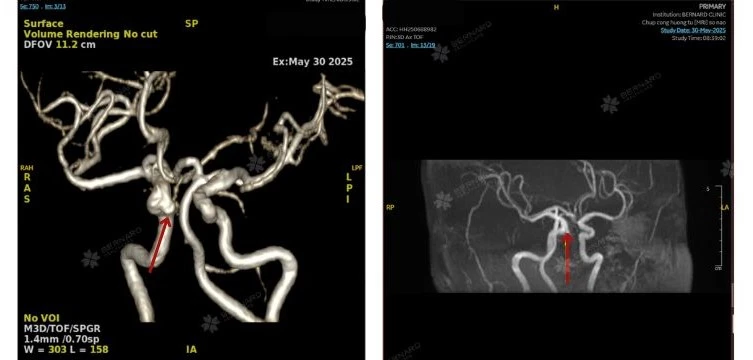

Hai tổn thương bất thường ở não và mạch máu não

Kết quả MRI của nữ bệnh nhân bất ngờ ghi nhận đồng thời hai tổn thương nghiêm trọng, tiềm ẩn nguy cơ lớn đến tính mạng nếu không được phát hiện và xử trí kịp thời.

- Túi phình mạch cảnh trong phải, đoạn mấu giường, hướng vào trong xuống dưới, kích thước khoảng 3 x 4mm.

Với trường hợp của chị N., túi phình có kích thước 3.0 x 4.0 mm, tuy chưa vượt ngưỡng nguy hiểm, nhưng vị trí gần nền sọ khiến tình huống trở nên phức tạp, cần theo dõi chặt chẽ và có kế hoạch can thiệp phù hợp.